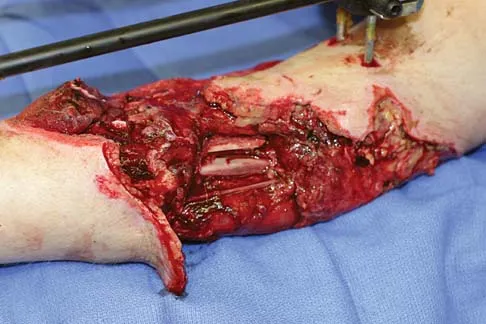

Question 21

A healthy 25-year-old man sustains a grade IIIB open tibial fracture. Following appropriate debridement, irrigation, and stabilization with an external fixator, the soft-tissue injury is shown in Figure 30. What is the most appropriate definitive soft-tissue coverage procedure?

Explanation